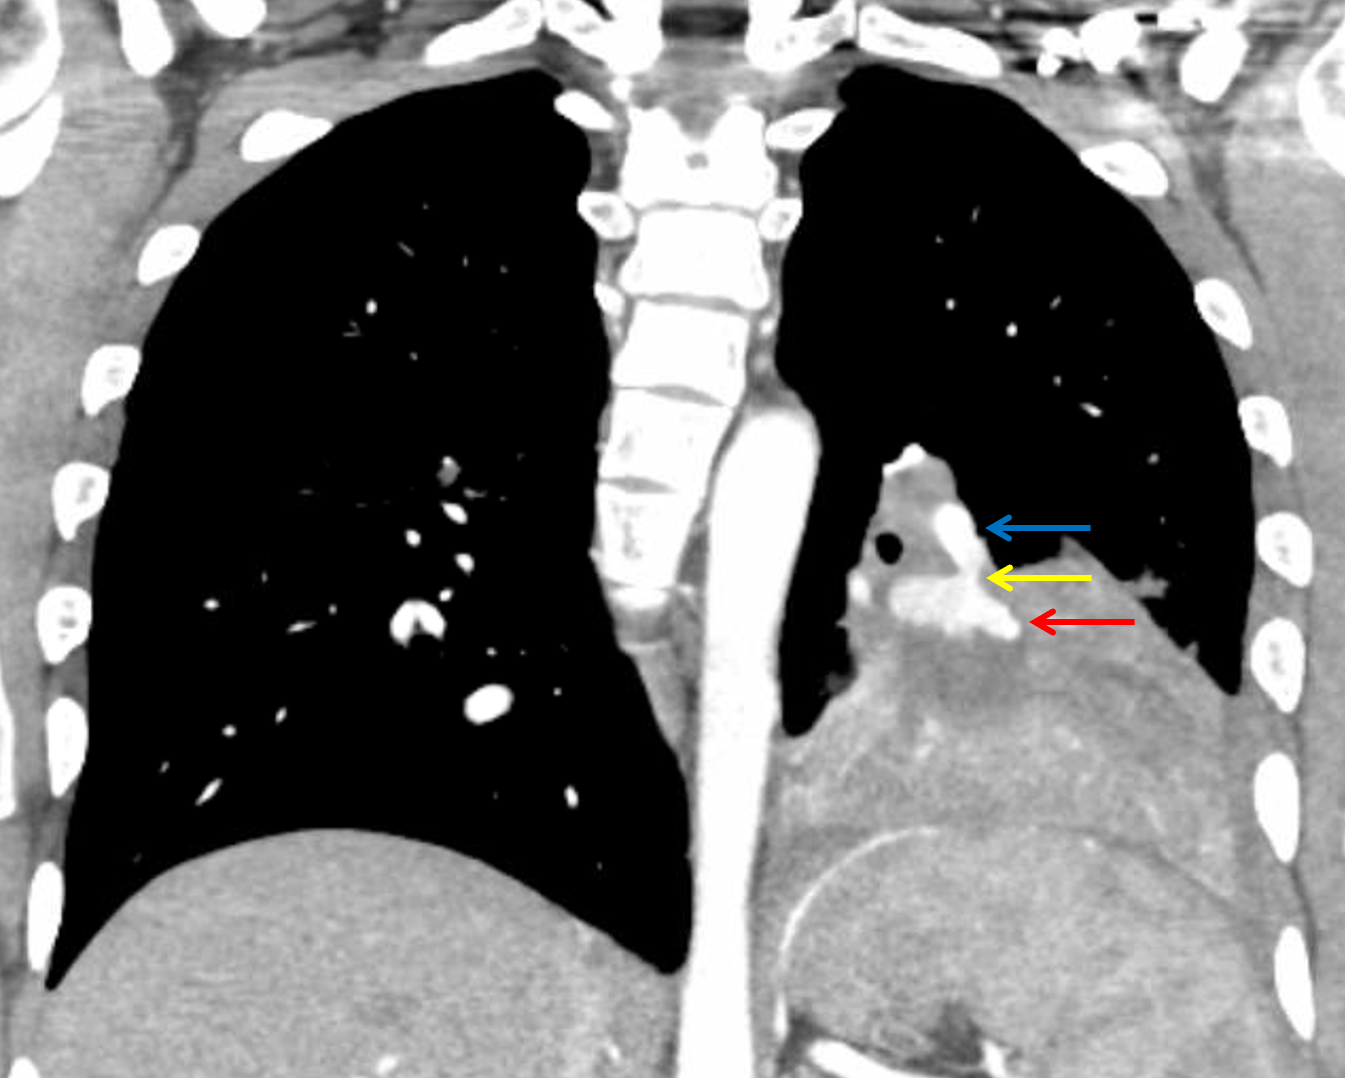

Sample ReportFindings concerning for necrotizing pneumonia in the left lower lobe with a large associated pulmonary arterial pseudoaneurysm. Recommend conventional pulmonary arteriogram and possible endovascular coiling.

Tree-in-bud nodularity in the left upper lobe is also concerning for pneumonia.

Cystic bronchiectasis in the right lower lobe, likely postinfectious.

Small left pleural effusion.